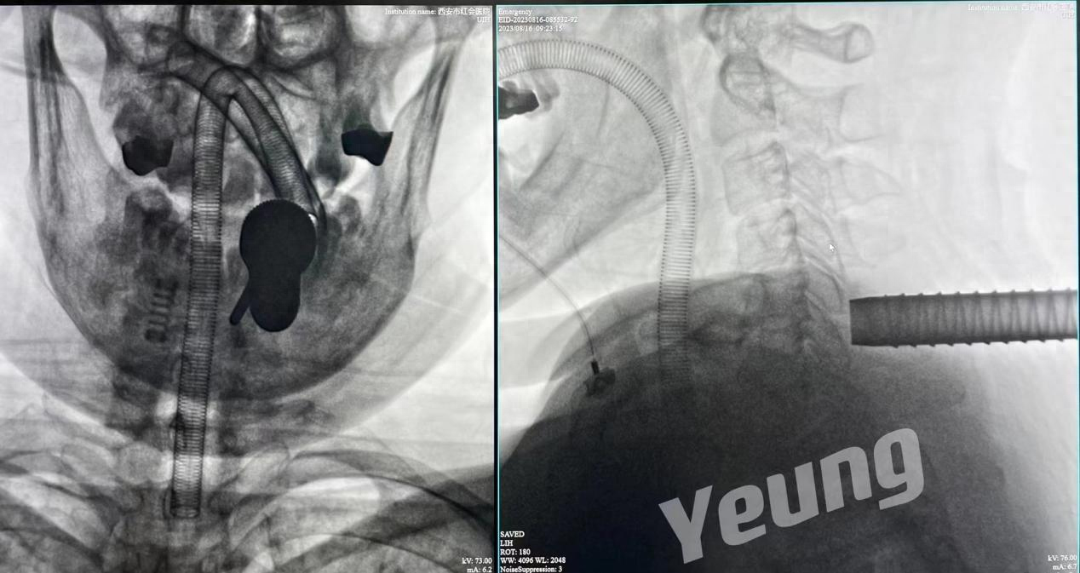

手术结束后当天患者症状明显缓解。复查影像资料显示神经减压良好、骨赘完全去除。

术后影像资料